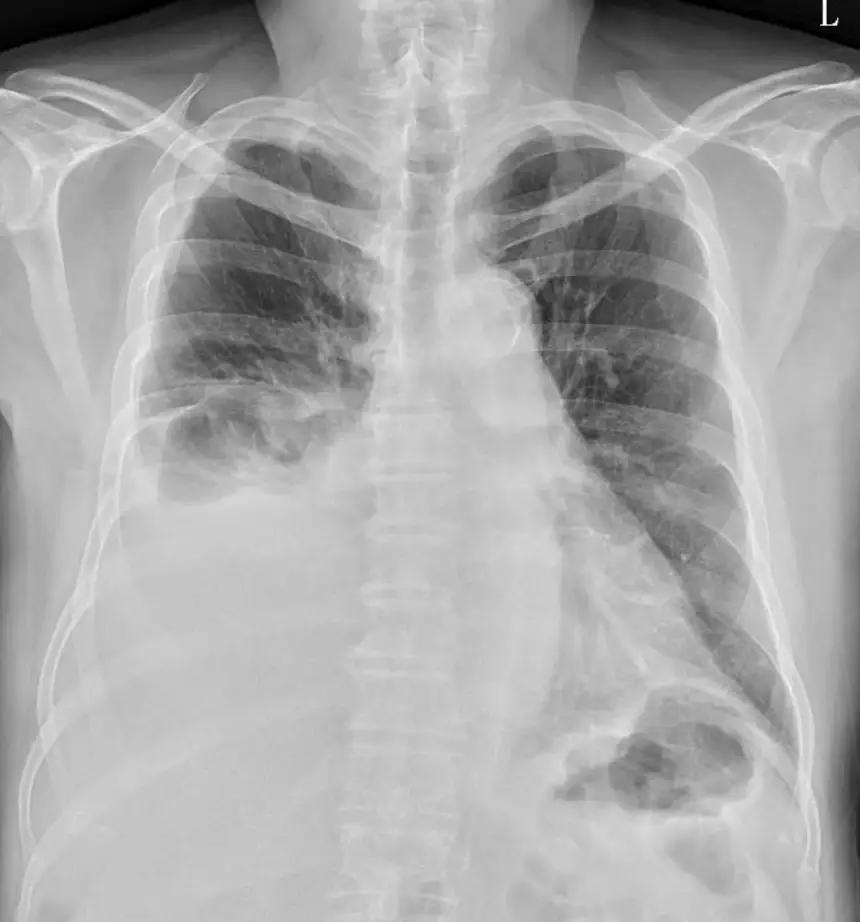

78歲男性,因咳嗽10天來門診就診。X光如附圖,右側肋膜積水抽出來顏色為黃色。其中total nucleated cells 1467/L,lymphocyte 87%,neutrophil 2%,mesothelial cell and histiocyte 11%,LDH 179 U/L,total protein 5.1 g/dL,pH 7.35,glucose 122 mg/dL,adenosine deaminae (ADA) 34 U/L,acid-fast染色: negative。請問關於接下來的處置,下列何者最不合適? 圖片描述

本題為一位 78 歲男性,右側肋膜積水,胸水檢查結果如下:

此胸水為滲出液(exudate),以淋巴球為主(87%),且 pH 正常、葡萄糖正常、LDH 僅輕微上升。鑑別診斷首要考慮惡性腫瘤(malignancy)結核性肋膜炎(tuberculous pleurisy)

本例完全不符合膿胸標準:pH 7.35(正常)、Glucose 122 mg/dL(正常)、LDH 179 U/L(低)、淋巴球 87%(非中性球為主)。因此「此胸水為膿胸,應直接置放胸管引流」是錯誤診斷與不當處置